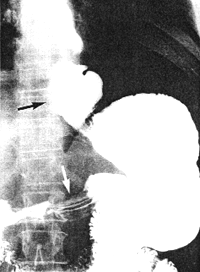

Case 32.1. E.B., 5 weeks old female infant, was admitted with a history of vomiting after feeds and recurrent bilateral pneumonia. Radiographic examination showed a severe, constant narrowing of the pyloric sphincteric cylinder, with a "string sign" typical of IHPS (Fig. 32.1A). The gastro-oesophageal junction was patulous with free and persistent gastro-oesophageal reflux, diagnosed radiographically as a sliding hiatus hernia (Fig. 32.1B). Some aspiration of refluxed barium occurred. At operation the next day a pyloric "olive" measuring approximately 2.3 cm x 0.8 cm, typical of IHPS, was found. Ramstedt pyloromyotomy was done; post-operatively vomiting stopped and the patient made an uneventful recovery.

A |

| Fig. 32.1 A,B. Case E.B. A Constant narrowing of pyloric sphincteric cylinder with string sign (arrows), typical of idiopathic hypertrophic pyloric stenosis. B Patulous gastro-oesophageal junction with free reflux (arrow) |

B |